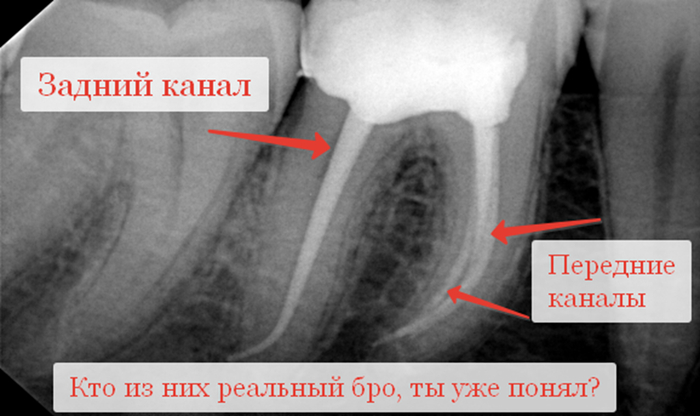

Многокорневая вкладка, как нам подсказывает Капитан Очевидность, фиксируется сразу в несколько корней. Это осуществимо, когда корни идут параллельно, например у верхней четверки. Если говорить про 6 и 7, где корни торчат рогаткой, то в дело вступают вкладки разборные, когда некоторые штифты делаются съемными и устанавливаются в момент фиксации вкладки через её культевую часть. Их философия заключается в том, что они мол лучше держатся в зубе за счет расклинивающего эффекта.

-Анатомия некоторых корневых каналов не всегда позволяет их распломбировать их так. Чтобы не ослабить потом зуб. Например, небный канал у верхних 6 и 7 зубов и задний канал у нижних, как правило, прямые, широкие, с толстыми стенками. Их легко найти, легко расширить до нужного размера, чуть ли не до самой верхушки. Если говорить про щечные и передние каналы, то они, как правило, узкие, кривые, с тонкими стенками, их устья находятся где-то в заднице. Также их корни имеют различные инвагинации и поднутрения, отчего даже просто их пролечить или запломбировать становиться проблемой, не то, что засунуть туда штифт и дать на него нагрузку.